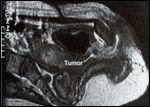

Magnetic Resonance Scan (MRI) of a Female Urethral Carinoma

The work-up for women with suspected urethral carcinoma includes cystourethroscopy, an excretory urogram, computed tomography (CT) of the pelvis and abdomen, chest x-ray, and magnetic resonance imaging (MRI) of the pelvis (Figure 3).